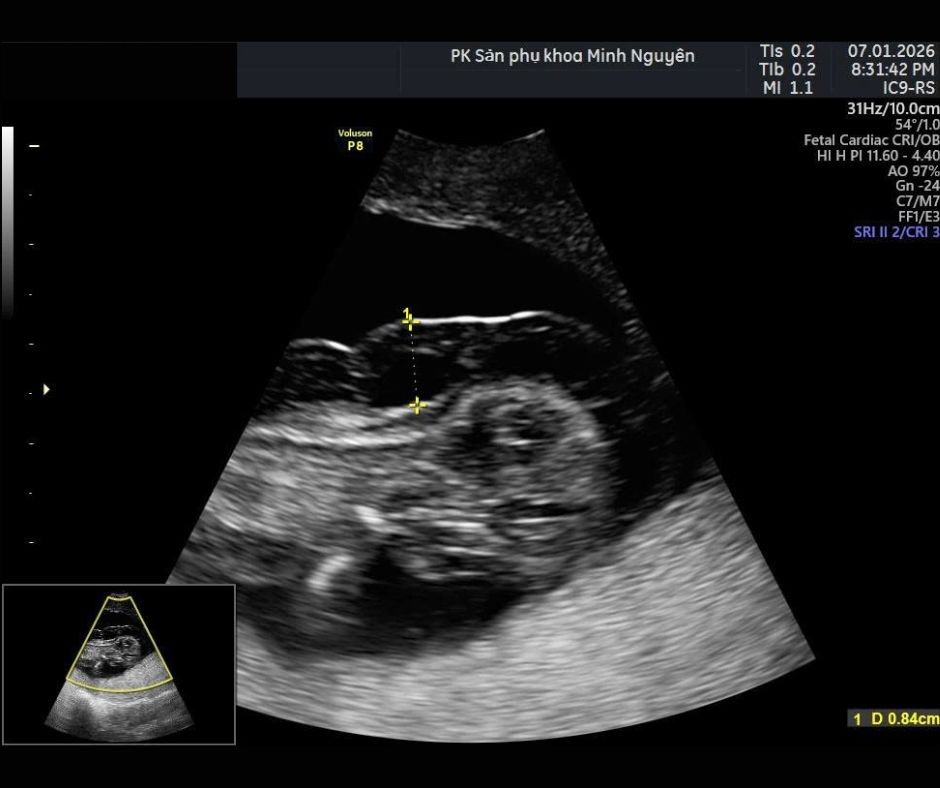

Dấu hiệu phù thai trên siêu âm

Siêu âm là phương pháp phát hiện chính. Các dấu hiệu thường thấy gồm:

• Da thai dày và phù nề

• Dịch quanh tim

• Dịch quanh phổi

• Bụng có dịch

• Bánh nhau dày

• Nước ối nhiều

Chẩn đoán phù thai thường đặt ra khi có ít nhất hai khoang chứa dịch.